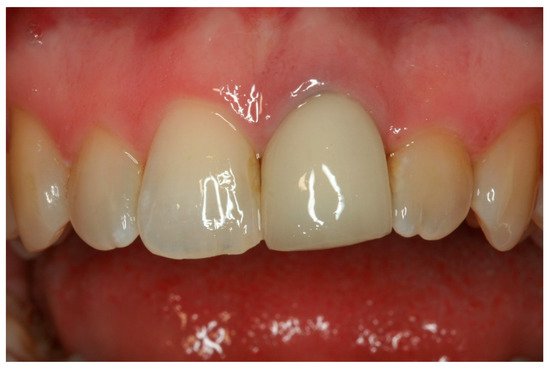

Ten Year Clinical and Aesthetic Outcomes of an Immediately Placed and Restored Implant in the Anterior Maxilla: A Case Report

3. Results